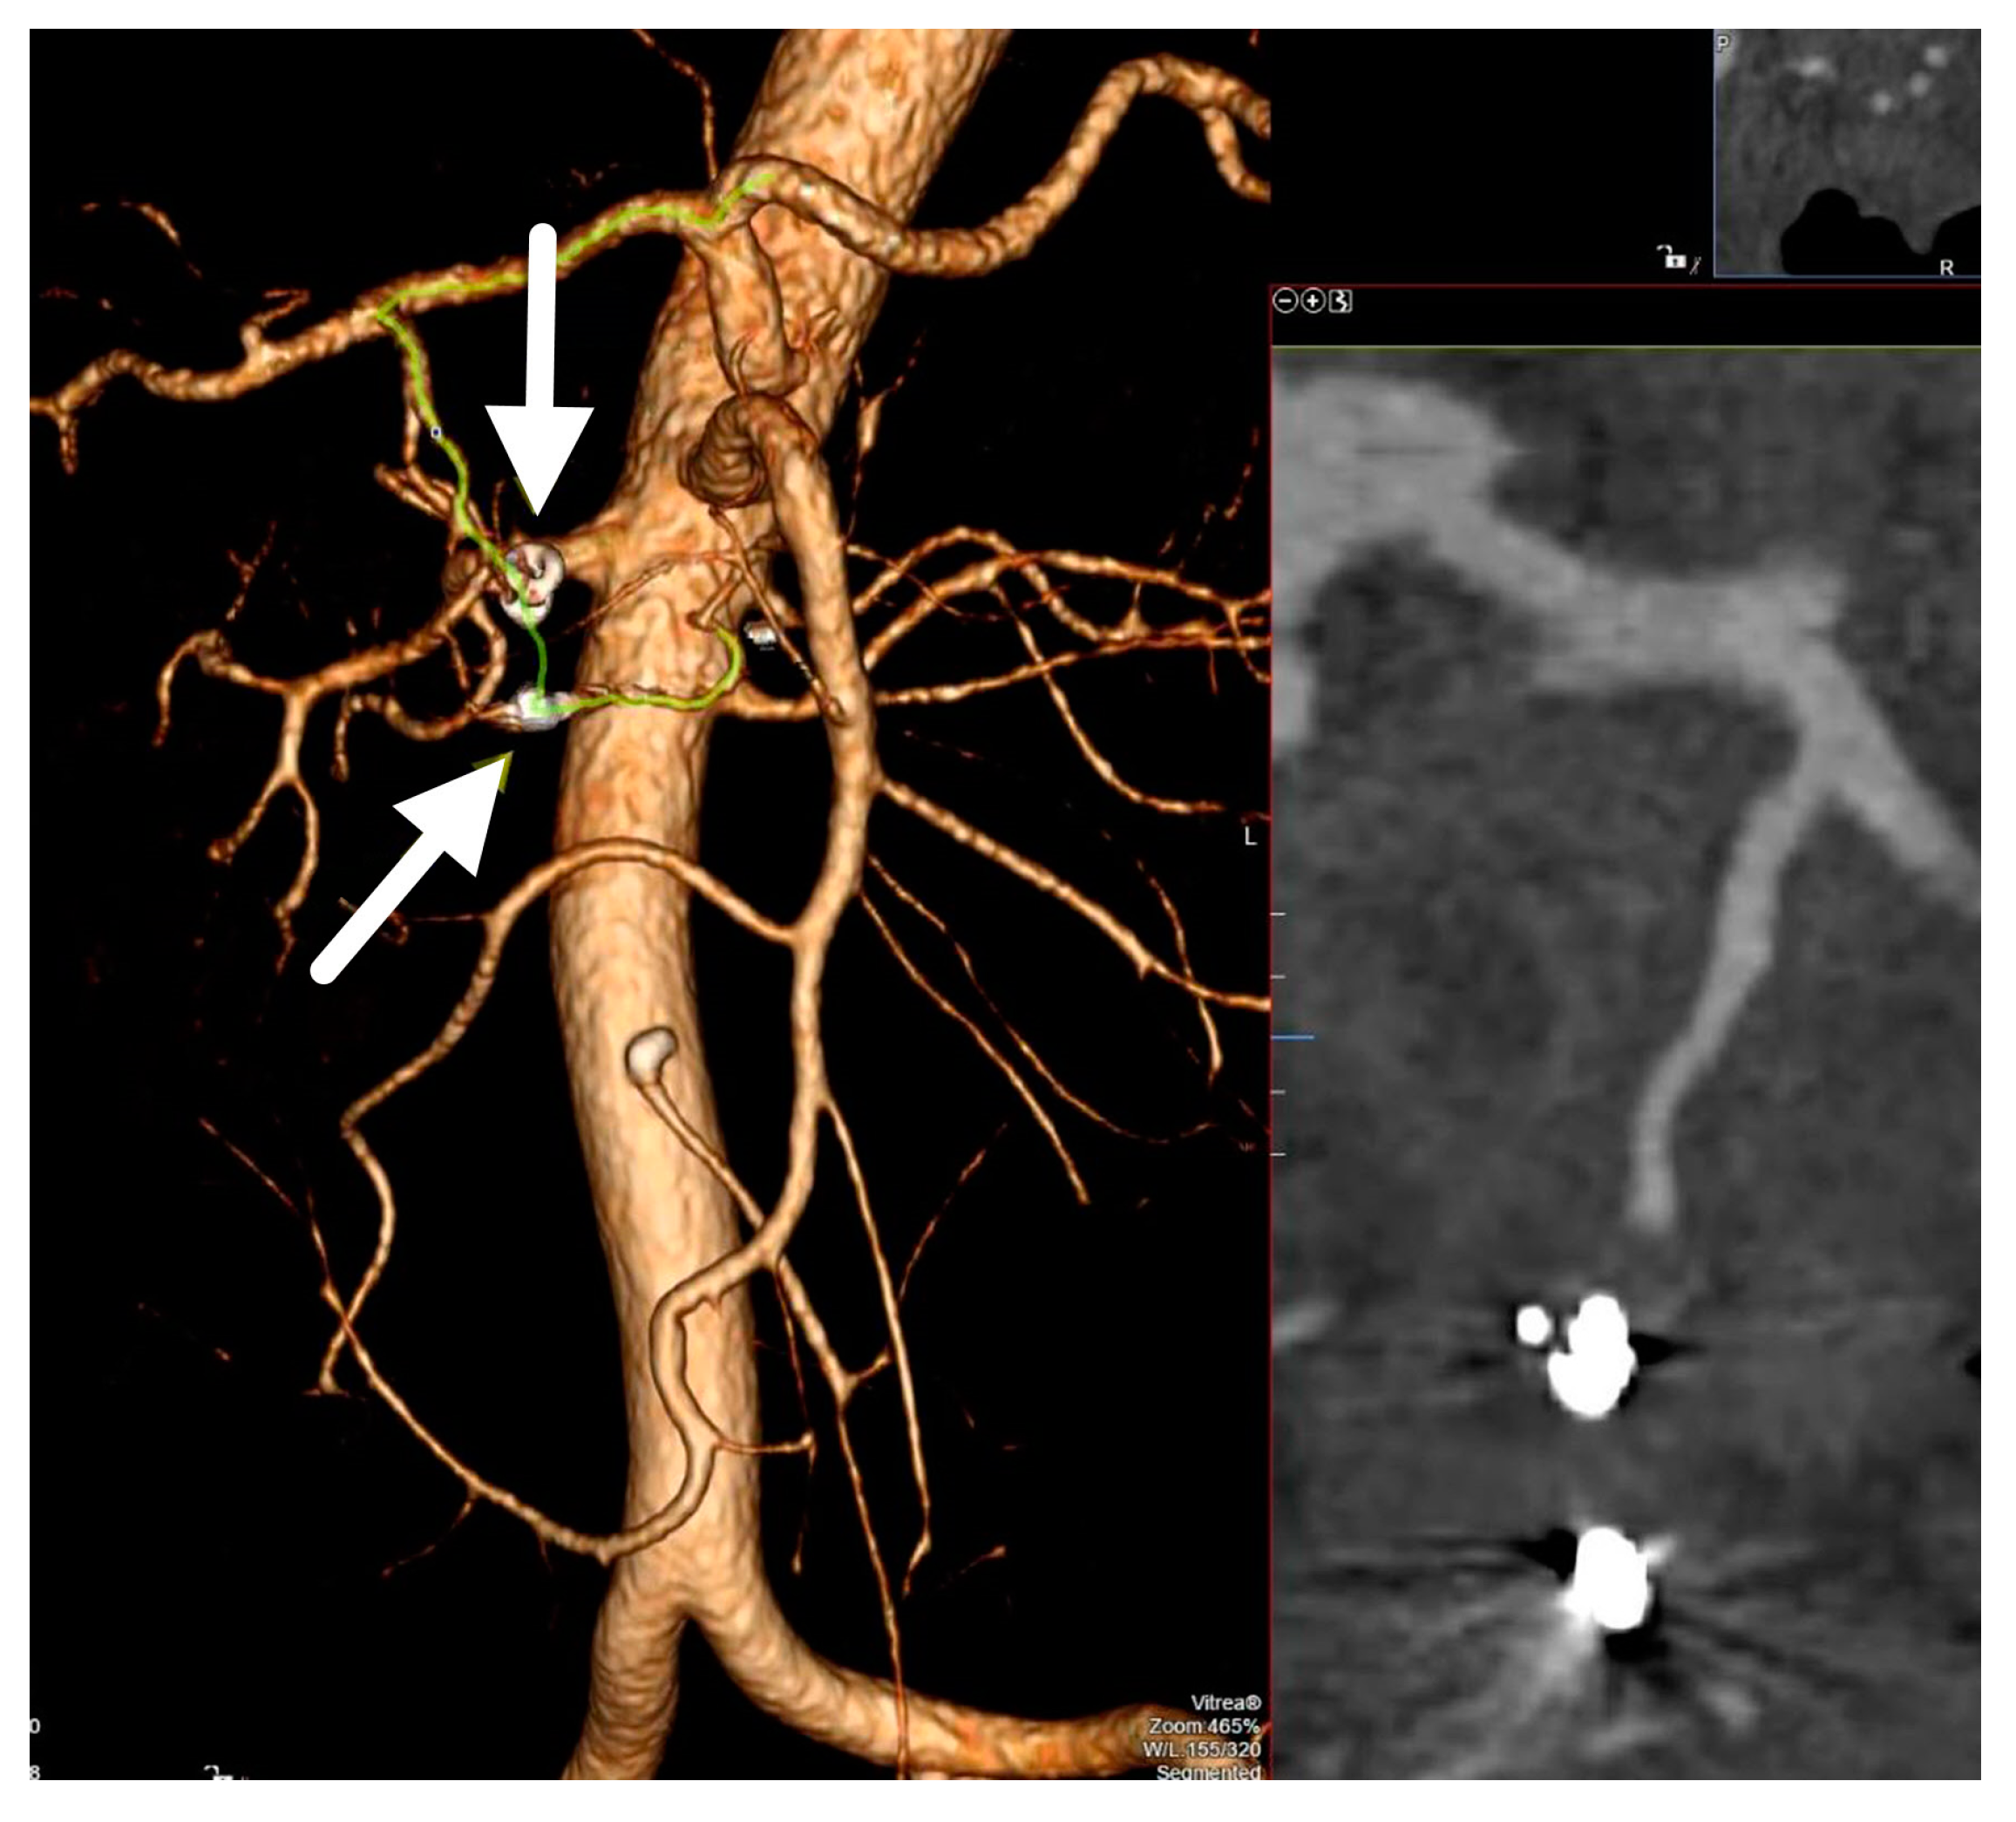

Successful Embolization of Posterior Inferior Pancreaticoduodenal Artery Pseudoaneurysm on the Grounds of Chronic Pancreatitis—Case Report and Literature Review

2. Case Report